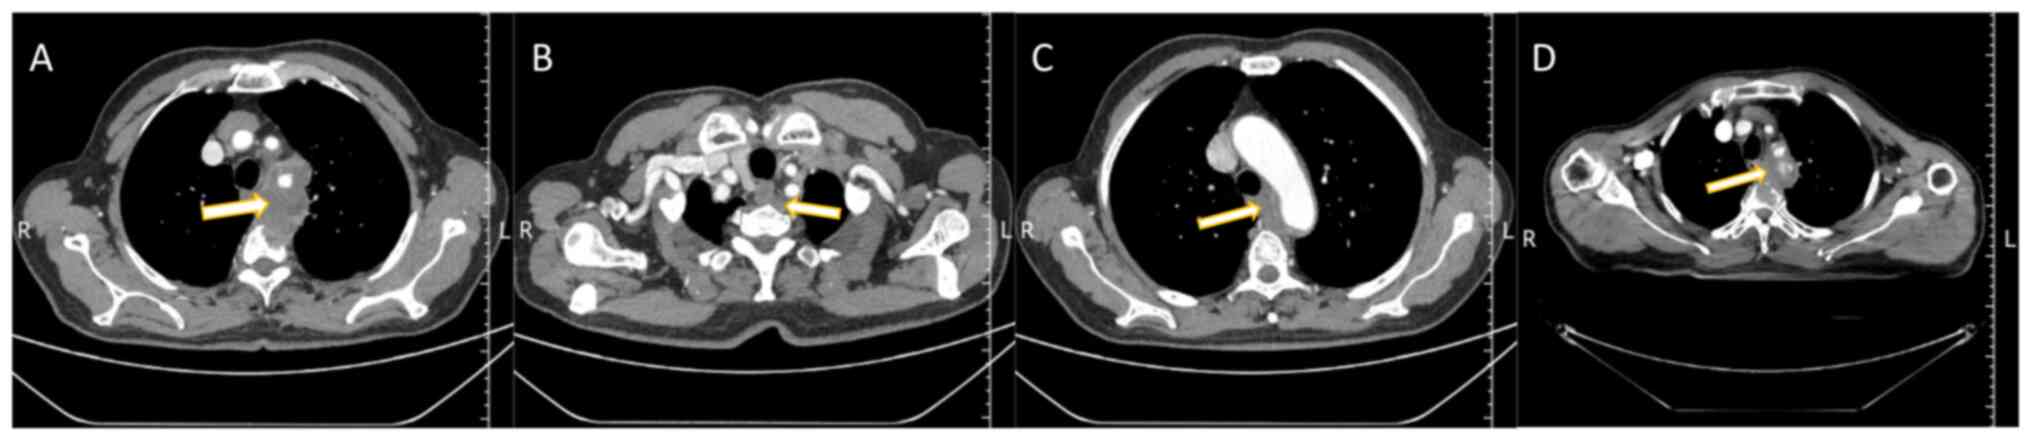

Figure 1.

Chest computed tomography scans of a 70-year-old male patient. (A) The largest cross-section of the mediastinal mass (arrow). (B) The upper border of the mediastinal mass (arrow). (C) The lower border of the mediastinal mass (arrow). (D) Reduced mediastinal mass (arrow) after radiotherapy.

Over the subsequent 5 months, the patient experienced worsening chest pain with a numerical rating scale (7) score of 2, and reported additional symptoms, including blood in the sputum, chest tightness and shortness of breath after physical activity. In late January 2023, a follow-up chest CT conducted at the Department of Cardiology of the Affiliated Hospital of Weifang Medical University (Weifang, China) revealed a soft-tissue density mass in the upper mediastinum posterior to the esophagus. The mass, with unclear boundaries, was ~68.5×45.9×60.0 mm in size. Additionally, there was evidence of bone destruction in the T2 and T3 vertebrae (Fig. 1A-C), suggesting the possibility of a malignant tumor. Subsequent examinations included a CT-guided biopsy of the mediastinal mass, and the postoperative pathology results identified the mass as a metastatic migratory cell carcinoma with a urothelial epithelial origin, characterized as a poorly differentiated carcinoma (tumor biopsy tissue was fixed with 10% neutral buffered formalin at 37°C for 6–8 h. Following gradient ethanol dehydration, xylene transparency and wax dipping, and embedding, the 3-micron paraffin sections were subjected to hematoxylin-eosin staining, where hematoxylin staining was performed for 6–8 min at 22°C and eosin staining was performed for 20–30 sec. Then gradient ethanol dehydration, xylene transparency, sealing, air drying, and finally the sections were successively observed and diagnosed under light microscope at 40 magnification) (Fig. 2A). Immunohistochemical (IHC) analysis yielded positive findings for p40 (cat. no. RMA-1006), cytokeratin 5/6 (CK5/6; cat. no. MAB-0744), p63 (cat. no. MAB-0694), GATA binding factor 3 (GATA-3; cat. no. MAB-0695), CK7 (cat. no. MAB-0828) and Ki-67 labeling index (40%) (cat. no. MAB-0672) (Fig. 2B-G) and negative findings for CD117 (cat. no. Kit-0029), CD5 (cat. no. MAB-0827), CD56 (cat. no. MAB-0743), synaptophysin (Syn) (cat. no. MAB-0742) and thyroid transcription factor-1 (TTF-1) (cat. no. MAB-0599). The paraffin-embedded tissue sections were stained with immunohistochemistry. The tissues were all fixed in 10% neutral buffered formalin at 37°C for 6–8 h. The paraffin sections with the thickness of 3 microns were rinsed with PBS liquid was washed three times, 5 min each time, then 3% methanol hydrogen peroxide liquid was dropwise added on the slides to block endogenous peroxidase (22°C, 10 min), PBS was washed once, and then the primary antibodies were dropwise added (all primary antibodies were purchased from ready-to-use antibodies of China Fuzhou Maixin Biotech, Co., Ltd.), Then incubated for 1 h in a wet box at the constant temperature of 37°C, and rinsed with PBS solution for 3 times, 5 min each time after incubation, then the secondary antibody (purchased from China Fuzhou Maixin Biotech, Co., Ltd., ready-to-use antibody, cat. no. KIT-5030) was added dropwise, and then incubated for 30 min at the constant temperature of 37°C in a wet box, rinsed with PBS solution for 3 times, 5 min each time, then DAB was added dropwise for 3–5 min, and the staining was stopped by washing with distilled water. The sections were observed under light microscope (magnification, ×40). All the analyses were conducted according to standard procedures. Brain magnetic resonance imaging (MRI) showed no metastases, and abdominal MRI revealed no primary lesions in the urinary tract. In February 2023, the patient's family sought a second opinion by taking the pathology slides to a referral hospital. After reviewing the initial puncture pathology findings and the consultation opinion from the referral hospital, the mediastinal mass was considered to be of urological origin. Consequently, the patient was diagnosed with occult UC with mediastinal metastases, without primary lesions in the urinary tract. After pre-treatment preparations, the patient started chemotherapy in February 2023. Two cycles of gemcitabine [1,000 mg/m2 on day 1, day 8, every 21 days (q21d)] and cisplatin (70 mg/m2 on days 1–2, q21d) chemotherapy were administered to stabilize the patient's condition, and osteoprotective treatment with inkadronate disodium (5 mg, q28d) was administered to address the vertebral destruction. Local radiotherapy for the mediastinal tumor and thoracic spine metastases was started 1 month later in April 2023, with a radiation dosage of 2 Gy/30 fractions. In May 2023, a follow-up CT scan was performed, revealing a reduction in the size of the mediastinal mass after radiotherapy (Fig. 1D). This finding led to an adjustment in the radiotherapy regimen; while the radiation dosage remained unchanged, the radiation field was reduced. The patient finished radiotherapy after 43 days. The patient experienced radiotherapy-induced esophagitis, manifesting as a feeling of obstruction during eating, for which a month of symptomatic treatment with continuous intravenous infusion of sodium riboflavin phosphate, intermittent intravenous infusion of sodium methylprednisolone succinate, and oral administration of Kangfuxin solution had been provided. Notably, the patient maintained good overall health and did not experience myelosuppression following the radiation therapy up to the time of writing this study. The patient had no obvious discomfort and had a good prognosis. The patient was asked to have a follow up every 2 months thereafter.